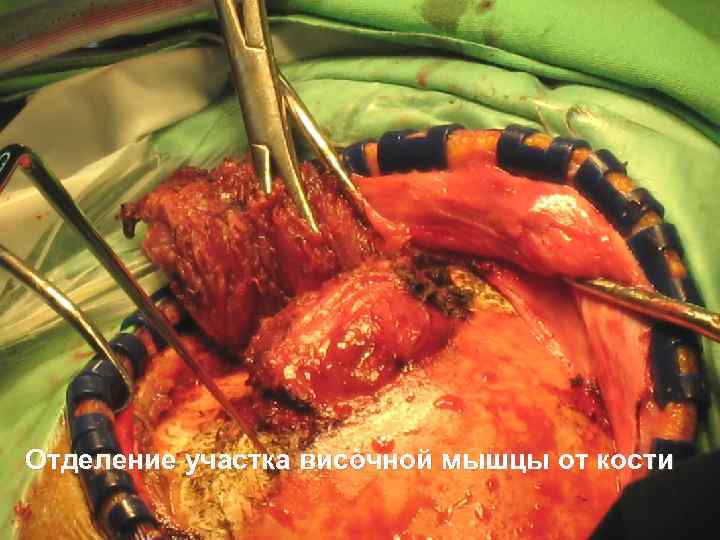

Отделение участка височной мышцы от кости 51